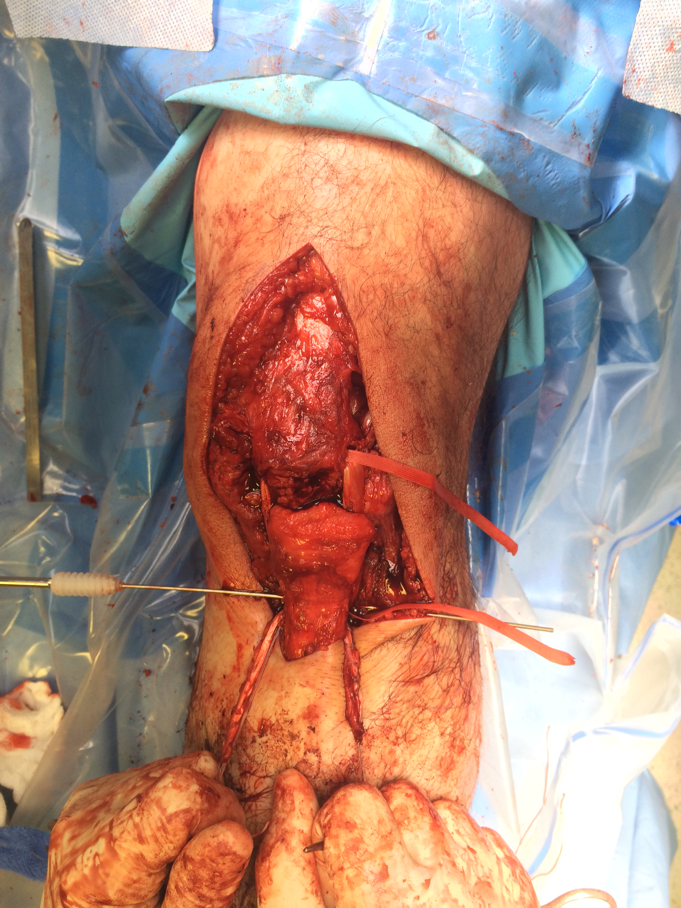

1. Tendon torn off patella

Multiple Bunnell / Krackow Sutures to Patella Tendon

- 2 non absorbable

- drill holes through patella ( 3 - 4)

- pass sutures and tie

- can augment with box fibrewire

Can reinforce with box wire loop

- large gauge wire 18G

- drill hole in tibial tuberosity

- transverse drill hole in patella

- pass in square and tie

- protects patella tendon

- problem is will break / irritate / need removal

- only do if concerned re repair

Test repair at end of case

- should be able to do some limited ROM

1. Semitendinosus autograft

- leave semitendinosus attached distally

- pass through distal pole patella

- reattach to tibia on lateral side